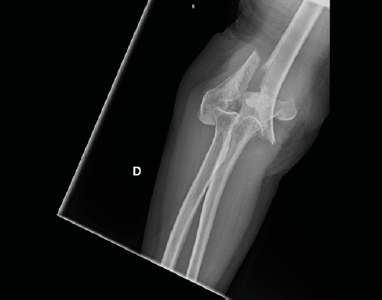

Figure 2.Right elbow X-ray at admittance in the emergency department.

A 70-year-old woman was admitted in San Jacopo Hospital in the Pistoia emergency department with the injury of the right elbow due to blunt trauma reported after a fall while she was walking home. X-ray (Fig. 2) and CT (Fig. 3) showed a supracondylar right humerus multiple fragment fracture with articular elbow dislocation. We classified the fracture as 13C3.1 according to the AO classification.